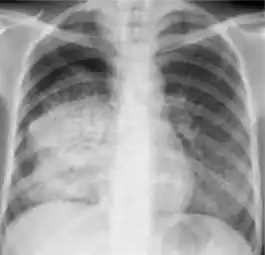

Dense homogenous opacity in right, middle and lower lobe of primary pulmonary TB. -

Chest x-ray showing patchy opacification on the upper right and mid-zone lung with fibrotic shadows, as well as bilateral hilar lymphadenopathy. -